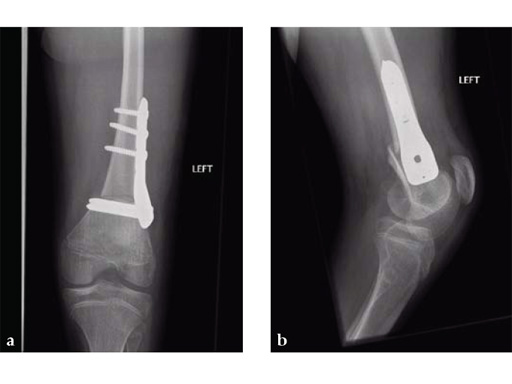

A 12-year-old girl presented for the first time to the cerebral palsy clinic. Although weak as well as spastic she was able to stand and step and wished to walk better. Physical examination revealed fixed flexion deformity of both knees. Distal femoral osteotomy with some shortening was the preferred option as hamstring lengthening and posterior knee capsule release would have caused further weakening.

Osteotomies were stabilized with the 5.0 mm LCP pediatric condylar plate. Postoperative management was non-weight bearing in splints, followed by weight bearing and rehabilitation at 6 weeks. Osteotomies healed uneventfully.